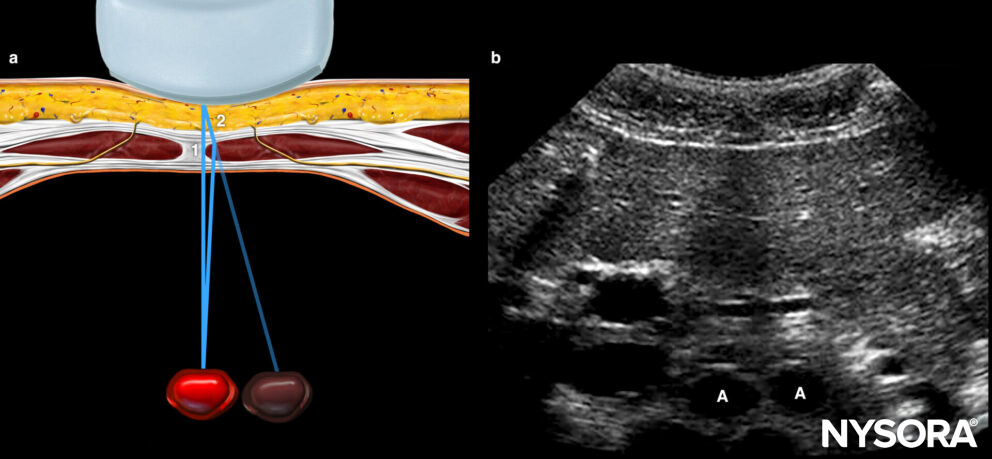

Refraction

Refraction is the appearance of the sound wave being bent when the ultrasound beam obliquely crosses an interface with tissues with different densities and, thus, different propagation speeds. It may result in an acoustic shadow at the interface boundary or a duplication artifact.

Illustration (a) shows how sound beam refraction results in a duplication artifact. (b) is a transverse midline view of the upper abdomen showing duplication of the aorta (A) secondary to rectus muscle refraction. The ultrasound figure was published in Atlas of Ultrasound-guided Procedures in Interventional Pain Management, Copyright Elsevier (2004).